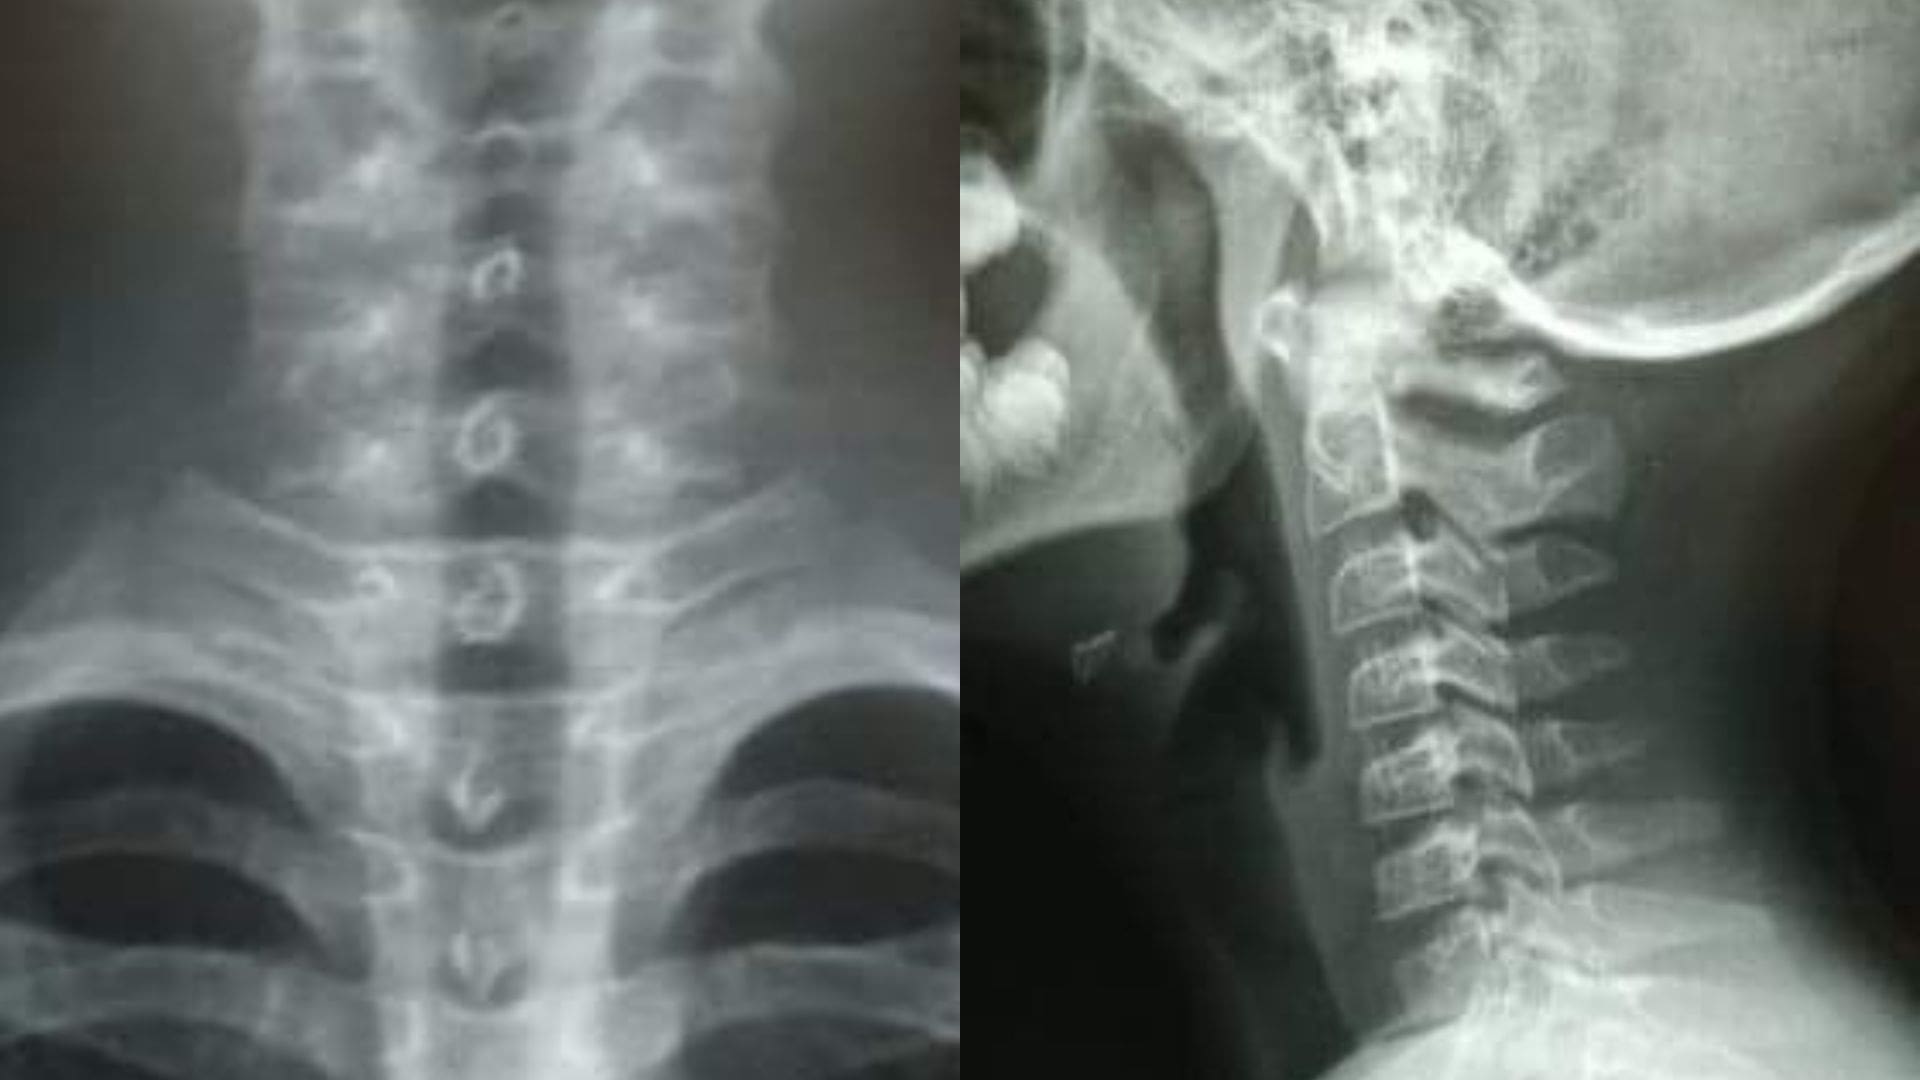

La madre del niño acudió al hospital donde le realizaron varios rayos x para determinar el daño que pudo sufrir tras la agresión.